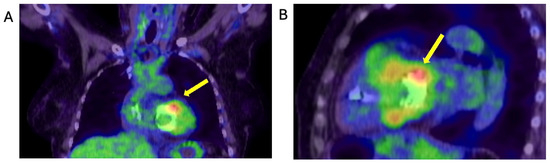

2.4. When the Diagnosis of IE Is Only Confirmed by the Tissue Culture of the Removed Degenerated tAVR